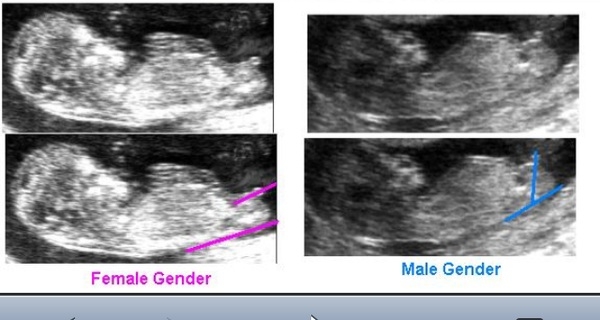

من از حالت پاهاش فهمیدم

بیشتر از این تصویر گفتم

مثل عکس پایینیه

دختره چون فکش کشیدس واینکه اون چیزش ب سمت پایینه